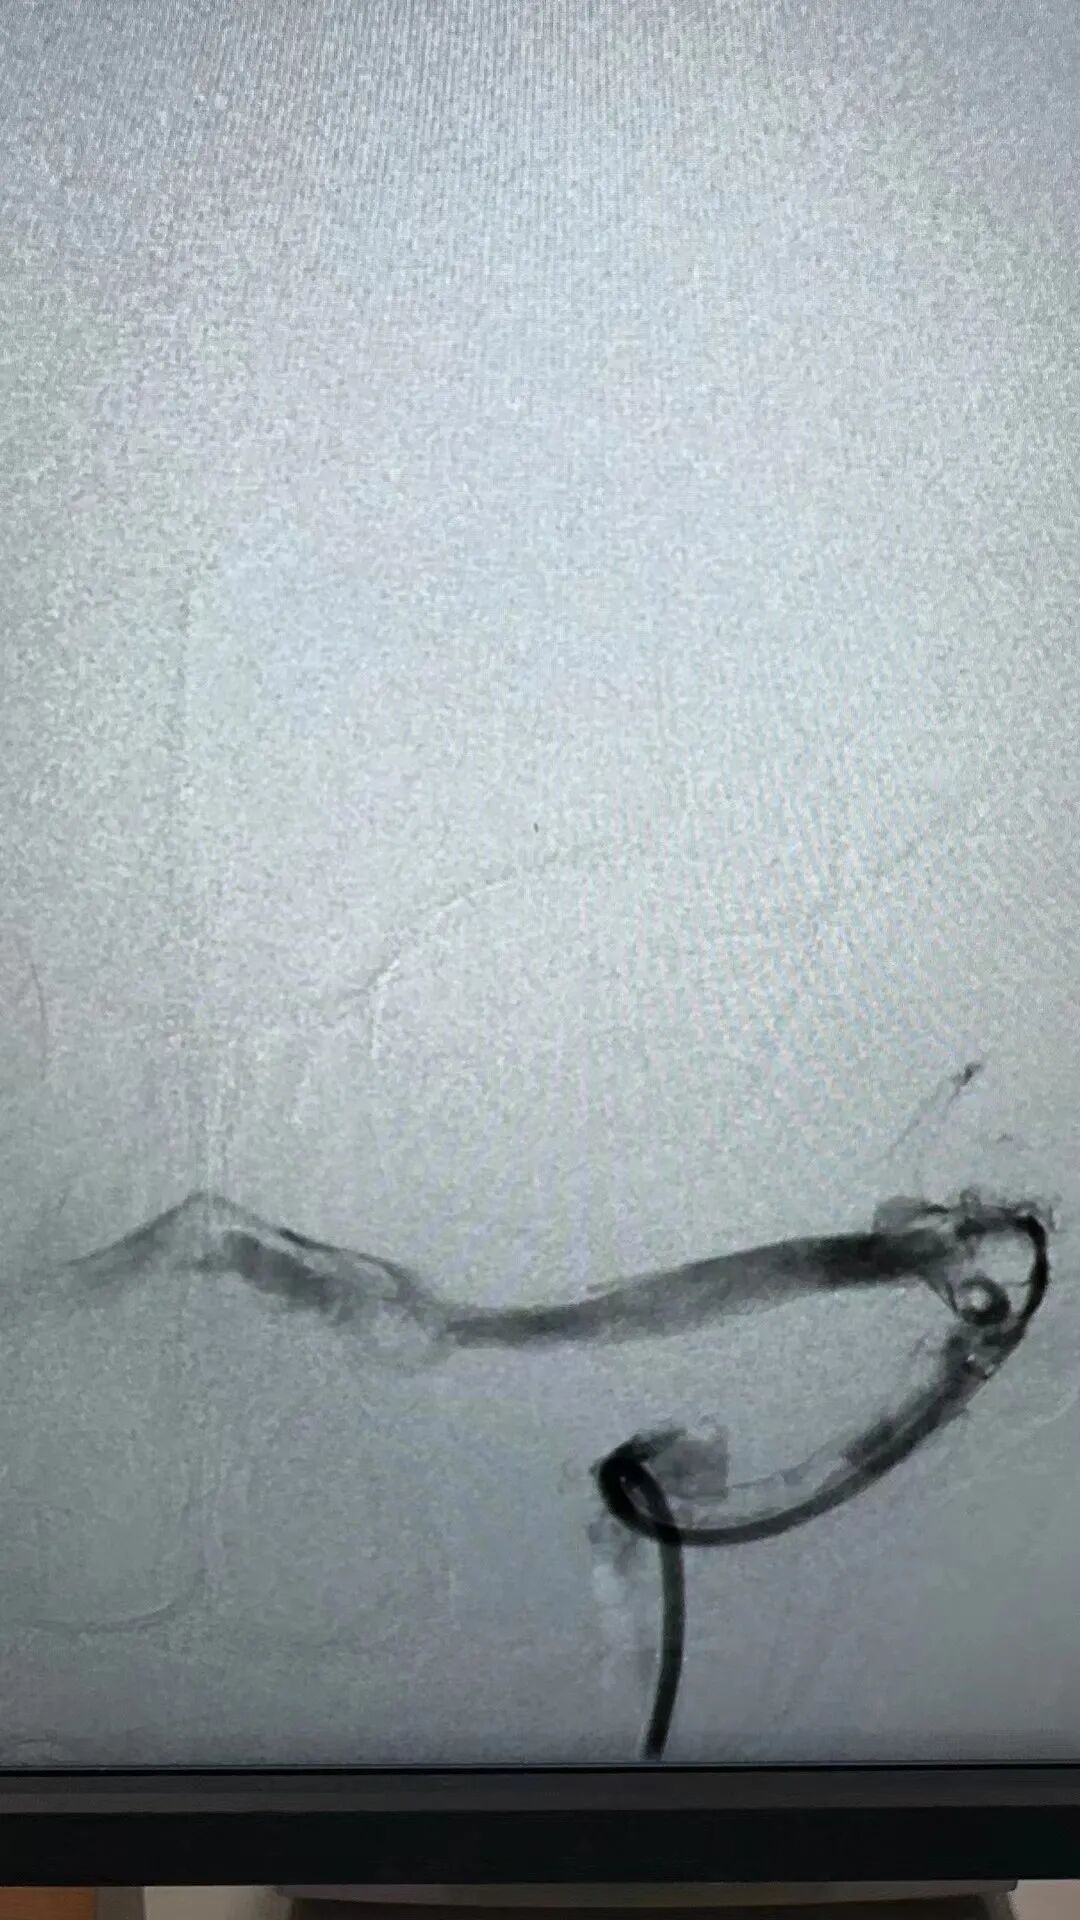

在充分準備后,景英朝治療團隊在麻醉科、介入導管室等多學科密切合作下,順利為患者行“顱內靜脈竇取栓術+腦靜脈竇溶栓術”,成功開通了阻塞的大腦靜脈及靜脈竇,患者轉危為安。

左頸總靜脈造影→左側橫竇血栓→完全再通